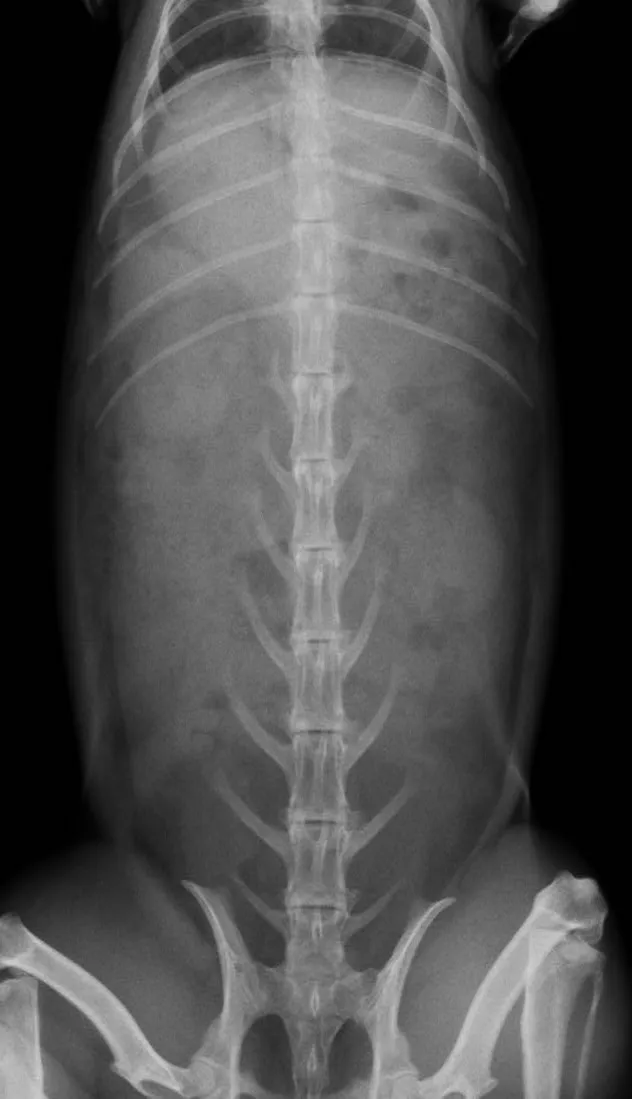

ウサギの食滞や毛球症、消化器機能不全(ウサギ消化器症候群:RGIS)の症状のことです。

胃内容、腸内容の停滞、ガス貯留、うっ滞、腸閉塞などの病態が複雑に関与して食欲不振、廃絶は起こります。

停滞が改善され、消化器の機能が回復する補助を様々行うのが治療ですが、功を奏しない場合は死亡することもあります。最近では内科的処置だけでなく、外科的処置で内容物の除去が行われるようになりましたが、ハードルは少々高めです。当院では内科的な治療の他に鍼灸治療や腹部のマッサージなどを併せて実施指導します。